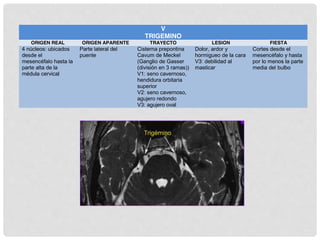

V TRIGÉMINO

OFTÁLMICA

V1

FISURA

ORBITARIA

SUPERIOR

MAXILAR

V2

FORAMEN

ROTUNDUM

MANDIBULAR

V3

OVAL

RAMA MOTORA VIAJA CON V3

Inerva el maseterino, el temporalis y el

pterigoideo

FIBRAS SENSITIVAS TERMINAN EN EL NÚCLEO

SENSORIAL PPAL EN EL PUNTE Y EN EL NÚCLEO

DEL TRACTO ESPINAL QUE SE EXTIENDE A LA

MÉDULA CERVICAL SUPERIOR

NÚCLEO MOTOR O MASTICATORIO SE

LOCALIZA EN EL PUENTE MEDIO JUSTO

MEDIAL AL NÚCLEO SENSORIAL

PRINCIPAL

Núcleo sensitivo

del V es el más

grande

En la médula crea

una elevación

lateral, el

tubérculo cinéreo

3 subnúcleos:

mesencefálico,

sensorial principal

y el núcleo del

tracto espinal.

NÚCLEO

MESENCEFÁLICO

Información

propioceltiva de los

músculos masticación

NÚCLEO SENSORIAL

PPAL

Sensación táctil de la

cara

NÚCLEO DEL TRACTO

ESPINAL.

Dolor y temperatura

Control reflejo de la

mordida

V1: división oftálmica V2: división maxilar V3: división mandibular